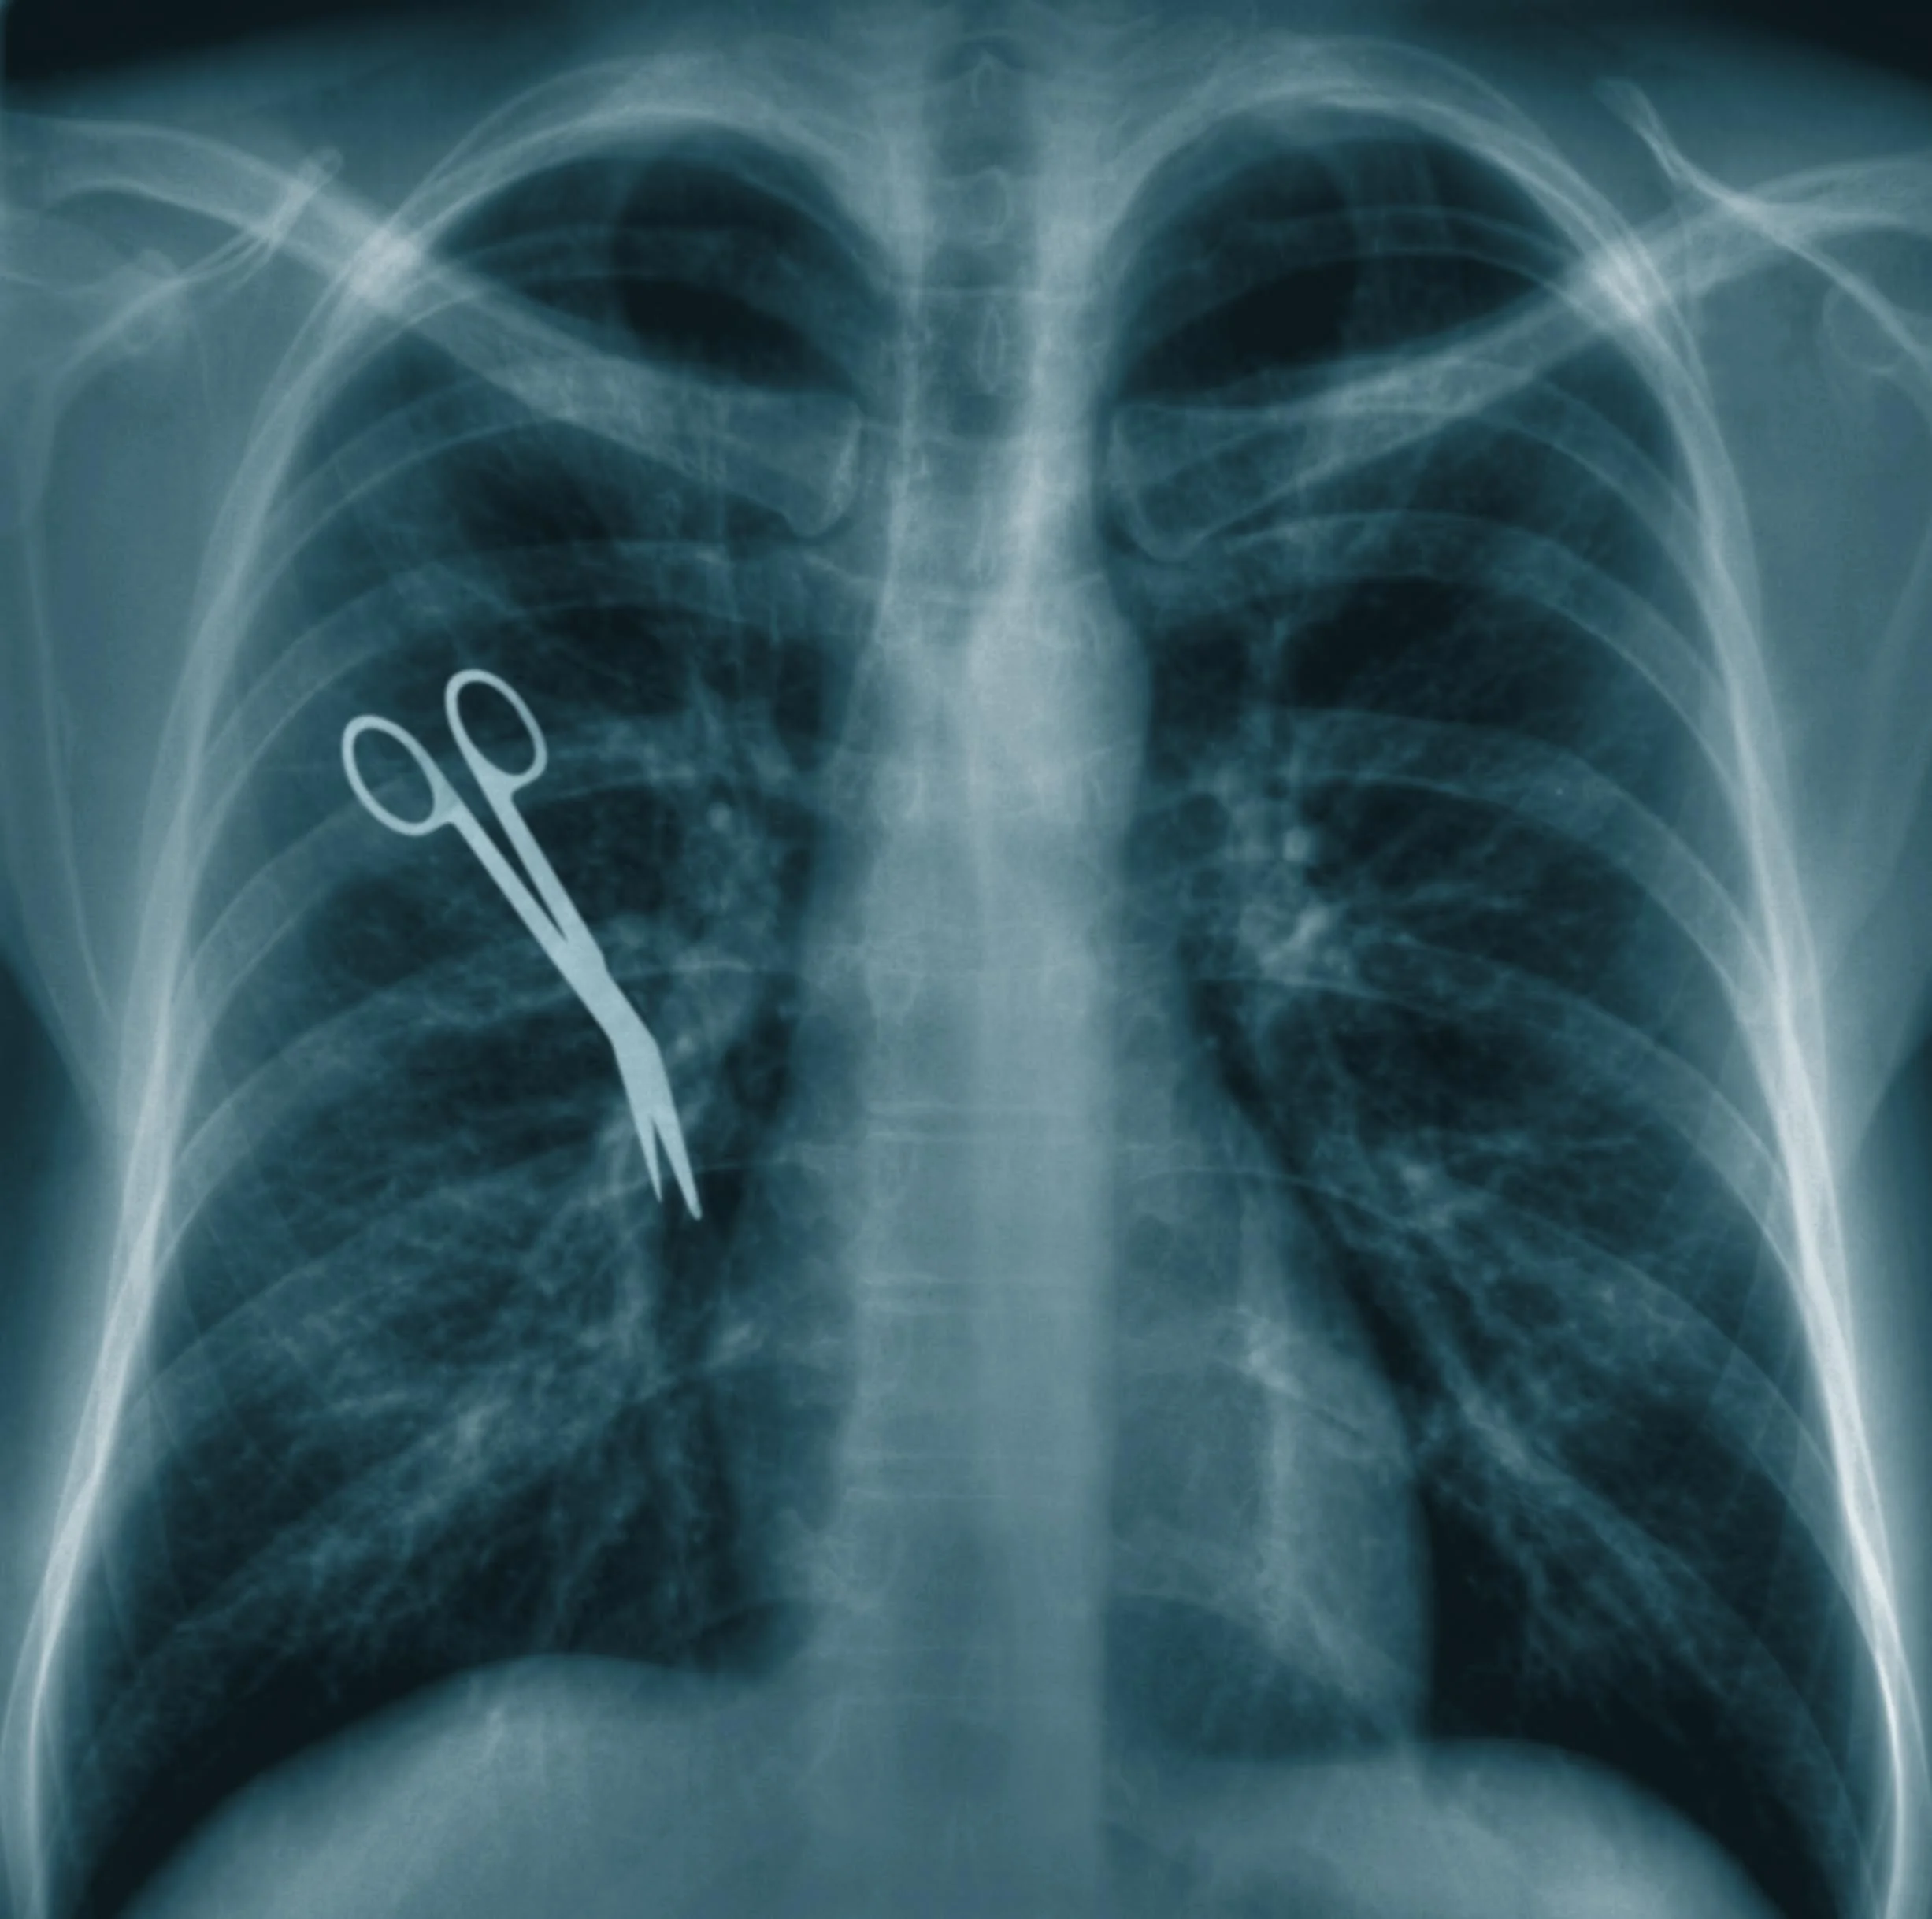

Surgery

Injury to bile duct during gall bladder operation, resulting in sepsis and other complications from permanently damaged bile duct

All of those cases resulted in a confidential settlement or trial verdict for the Plaintiff.